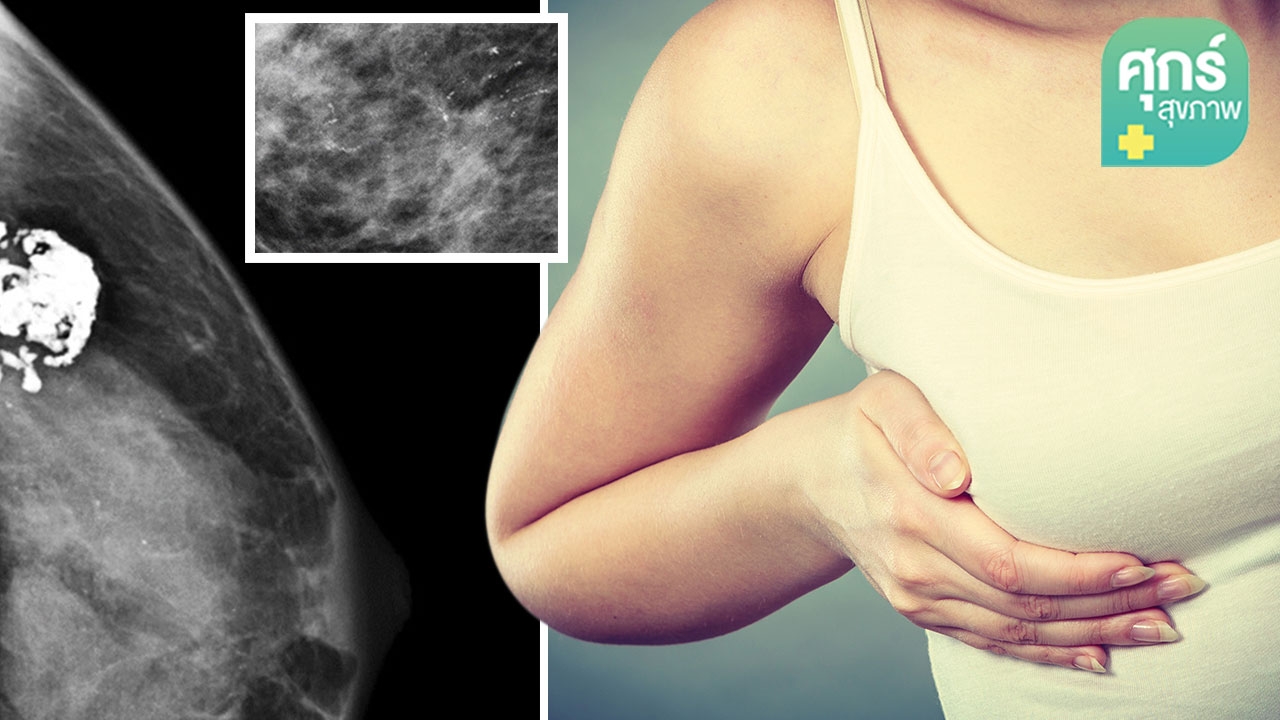

“มะเร็งเต้านม” เป็นมะเร็งชนิดที่พบมากที่สุดในผู้หญิงไทย จึงเป็นอีกโรคที่ผู้หญิงทุกคนควรหันมาให้ความใส่ใจและเริ่มตรวจคัดกรองมะเร็งเต้านมกันตั้งแต่เนิ่นๆ ซึ่งวิธีที่เหมาะสมที่สุดในการตรวจหามะเร็งเต้านมก็คือการตรวจด้วยเครื่องแมมโมแกรม

การตรวจพบหินปูนที่เต้านมจากแมมโมแกรม ไม่ใช่เรื่องที่อันตรายในทุกกรณีไป เพราะใช่ว่าหินปูนที่พบเหล่านั้นจะเป็นหินปูนที่นำไปสู่การเป็นมะเร็งเต้านมทั้งหมด การตรวจคัดกรองด้วยเครื่องแมมโมแกรมจึงเป็นวิธีการตรวจที่ให้ประโยขน์มากในแง่การตรวจหาหินปูนชนิดที่เป็นระยะแรกของมะเร็งเต้านม เพราะถ้าหากเราสามารถพบความผิดปกติดังกล่าวได้ตั้งแต่เนิ่นๆ ก็จะนำมาสู่การรักษาที่ให้ผลดีต่อคนไข้มากที่สุด